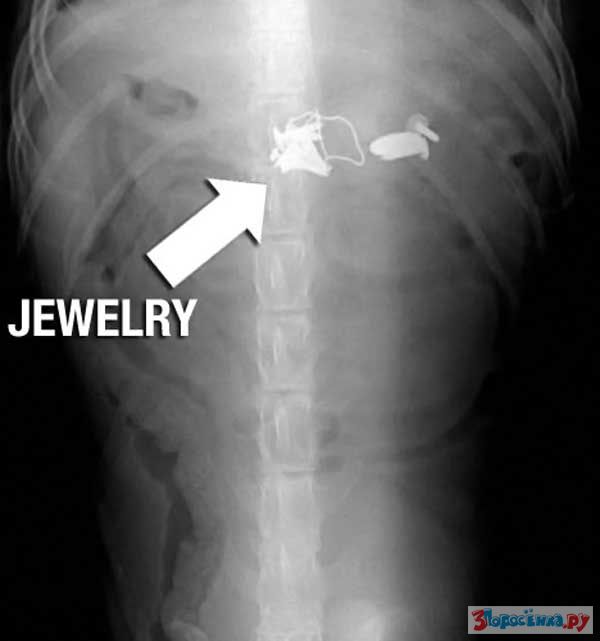

Нет ничего не перевариваемого

Некоторые собаки видимо полагают что их желудок способен переварить все на свете.